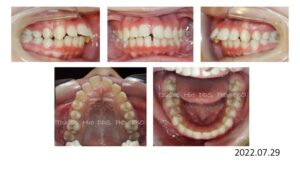

8歳の時、I市の歯科医院で、顎が狭くて歯が入りきらない、顎を拡げなければいけないといわれ、治療を開始したそうですが、6年経っても治療が終わらないどころか、写真のように全く噛み合っていないために、14歳の時にセカンドオピニオンで ひろ矯正歯科に来られました。

臼歯関係は、右が 4㎜ II級。左が 7㎜ II級で、7番しか咬合しておらず、著しい開咬を呈していました。

これは、拡大を始める前の写真ですが、口腔内写真を見る限り、拡大する必要はないです。

8歳からリンガルアーチで拡大を開始し、3年間拡大を続け、12歳でマルチブラケットを付けて治療を開始したそうですが、開咬が治らないためにアンカースクリューを4本打って治療を続けたとのことです。

こんなスクリューじゃあ何の意味もありません。

まさにやっている事がデタラメです。

ひろ矯正歯科に来られた時には、口腔内清掃状態は悪く、全ての歯が齲蝕でボロボロ、要治療でした。

治療中はブラッシング指導は一切無かったそうです。

検査、診断の結果、この患者さんは矯正のみで治療することは不可能、上下顎骨の離断が必要で外科矯正となりました。

この患者さんも歯が入らないから、顎を拡げましょうと言われ拡大を続けましたが、治療前の状態をみると、判断を誤っていることがわかります。